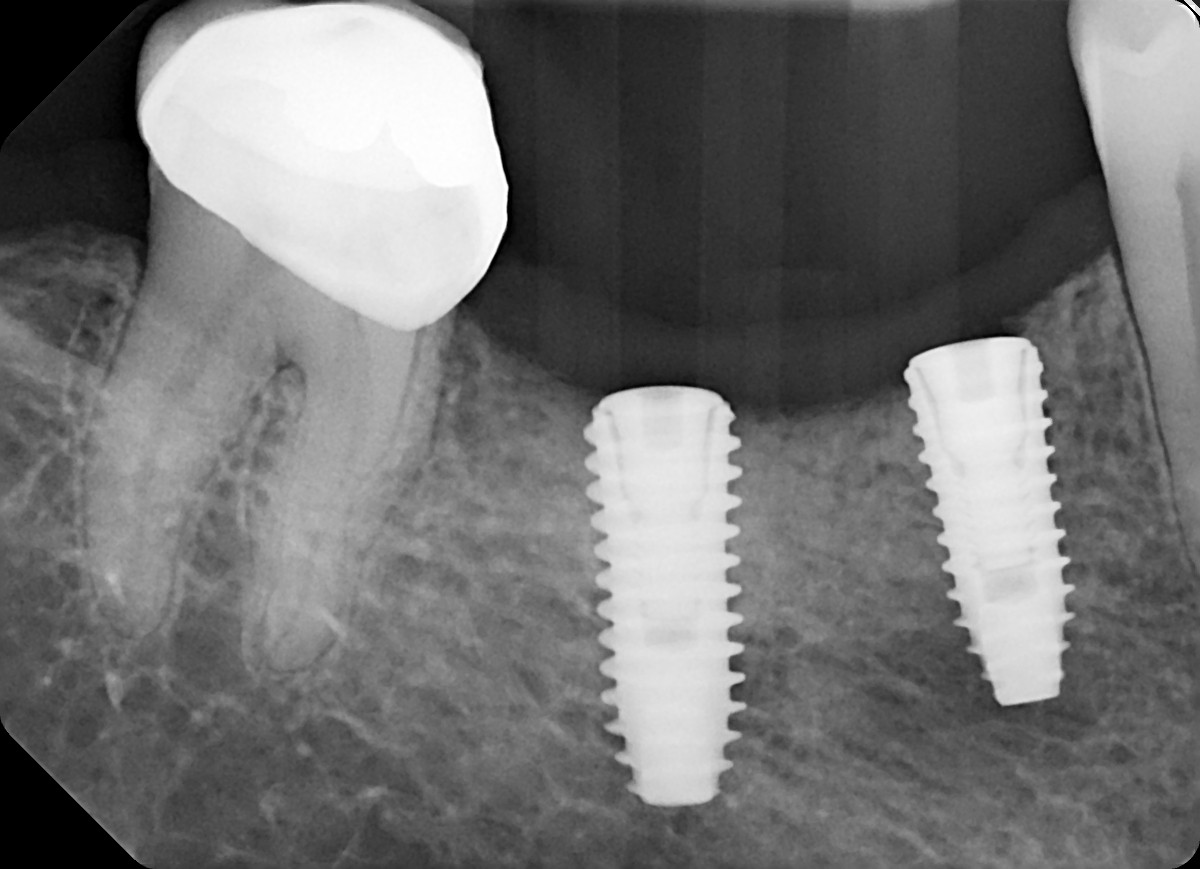

22. What option can be selected for the crown over the implant?